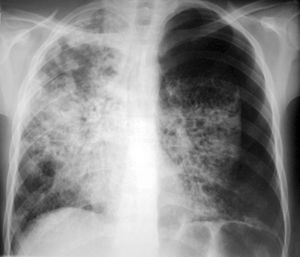

Mi torax

como lo ven?